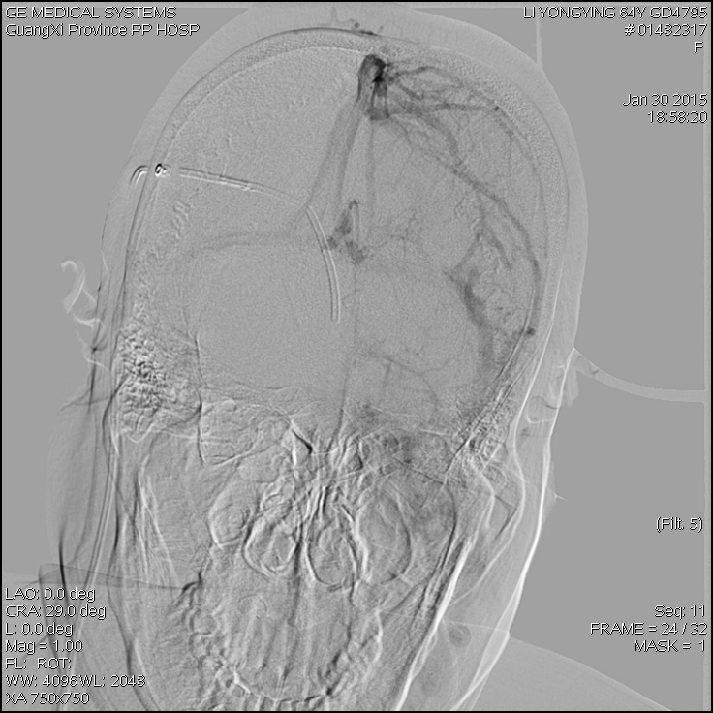

2015-1-30 DSA